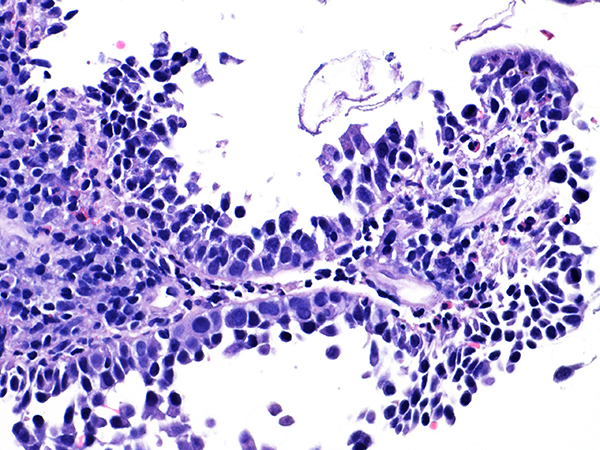

Case 7

Soft ECC CIN 2

40x - High Power